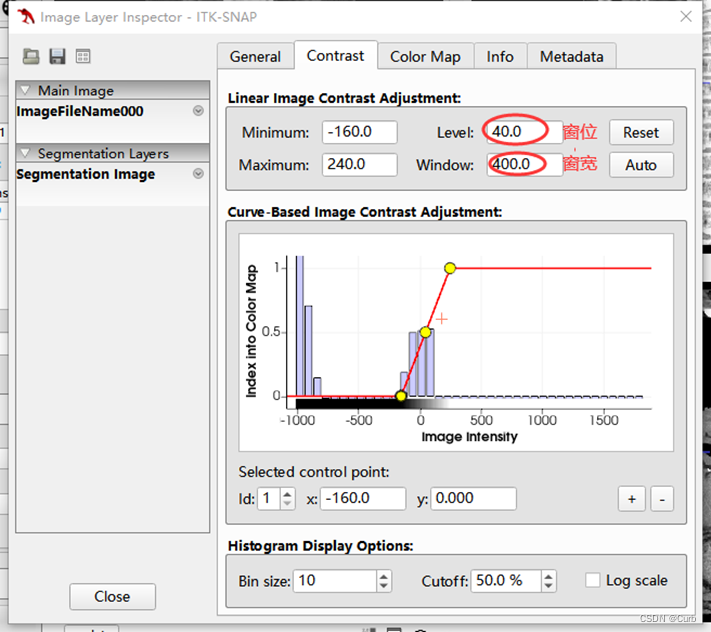

3 窗宽窗位调节

纵隔窗可观察心脏、大血管的位置,纵隔内淋巴结的大小,纵隔内肿块及这些结构的比邻关系。

纵隔窗:

窗位30 Hu~50 Hu;

窗宽300 Hu~500 Hu,

肺窗:

窗位-600 Hu ~ -800 Hu,

窗宽1300 Hu~1700 Hu,

在上述基本窗宽的基础上,若观察肺裂和肺血管,可调窄窗宽和调低窗位,对肿块形态,分叶,胸膜凹陷征,毛刺征增的观察肺窗比纵隔窗更为清晰。

先点击Tools,再点击Color Map Editor,出现以下画面,通过修改Level和Window来调节窗位和窗宽。这里根据以上参考,设置窗位为40,设置窗宽为400(可以发现心脏各部分的轮廓很清晰)。